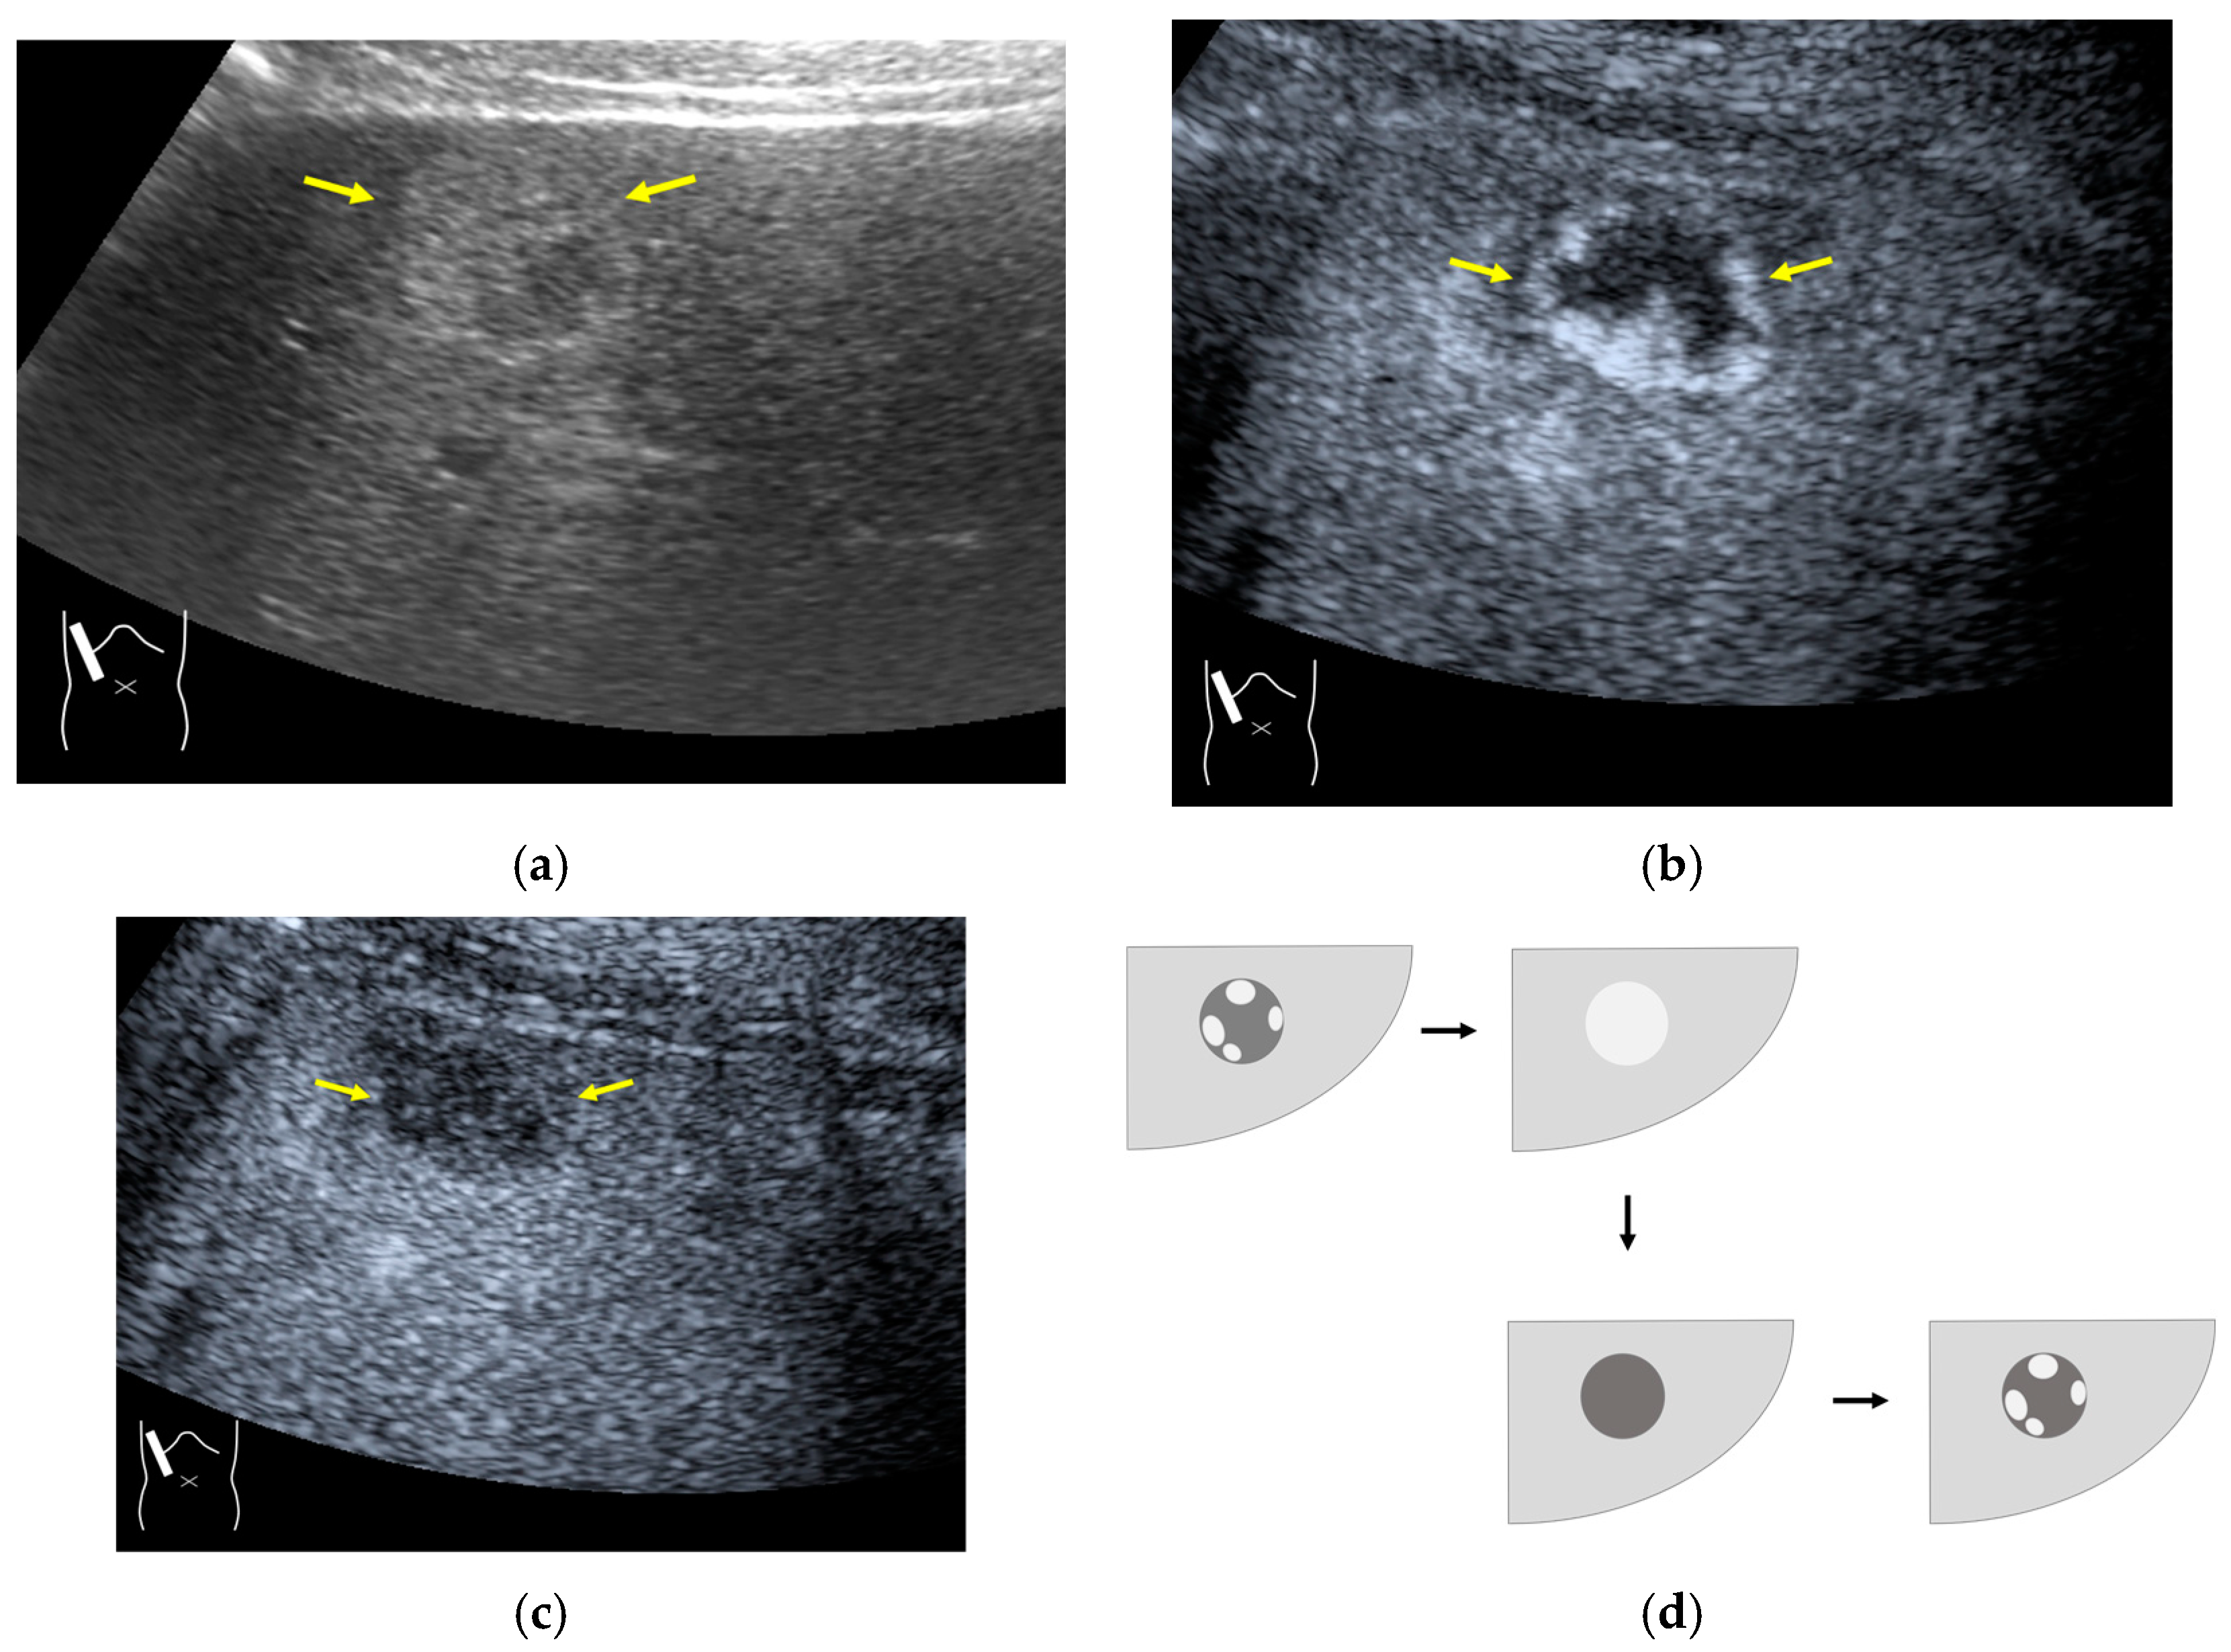

3.2.1. Microbubble Destruction Artifacts

3.2.2. Prolonged Heterogeneous Accumulation Artifacts

3.2.3. CEUS-Related Posterior Echo Enhancement